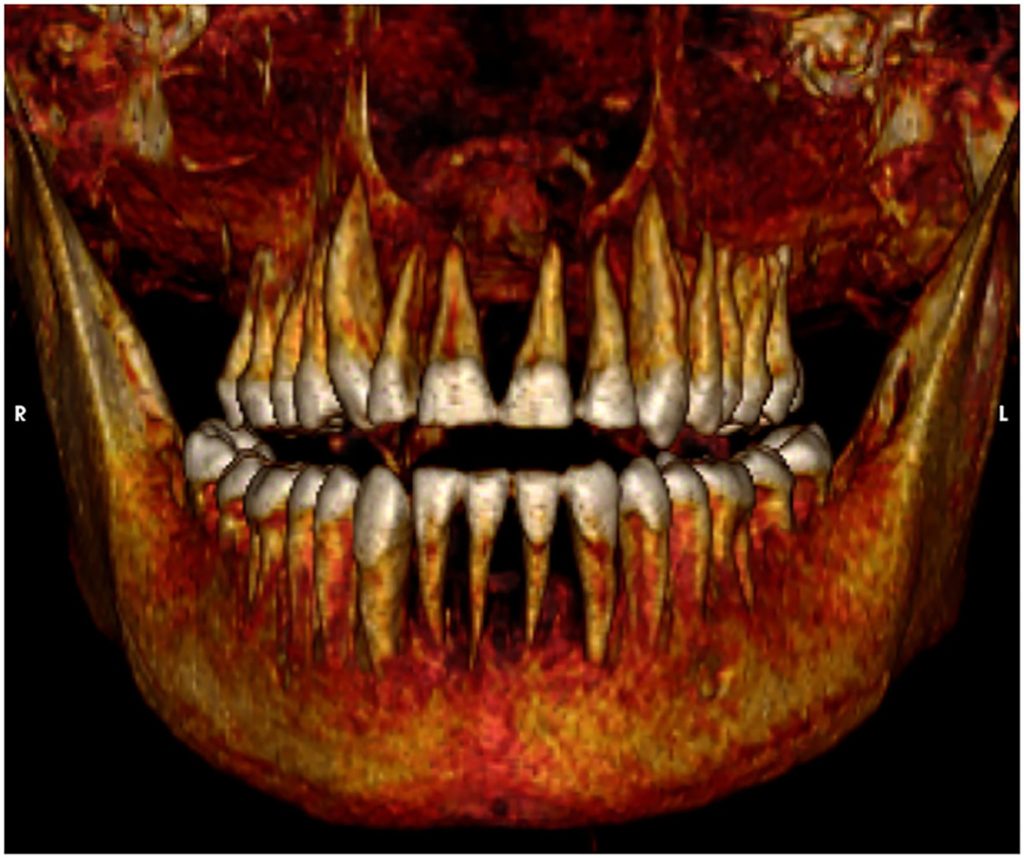

His brain was also undisturbed — perhaps one of the few remaining royals during Late Period ancient Egypt to have kept it, as the process of removing the brain, bit-by-bit through the nose, was popularized around 3,500 years ago. He also died with a healthy set of teeth, and was evidently circumcised, as was tradition.

He “seems to have physically resembled his father,” Ahmose I, according to Saleem. “He had a narrow chin, a small narrow nose, curly hair and mildly protruding upper teeth.”